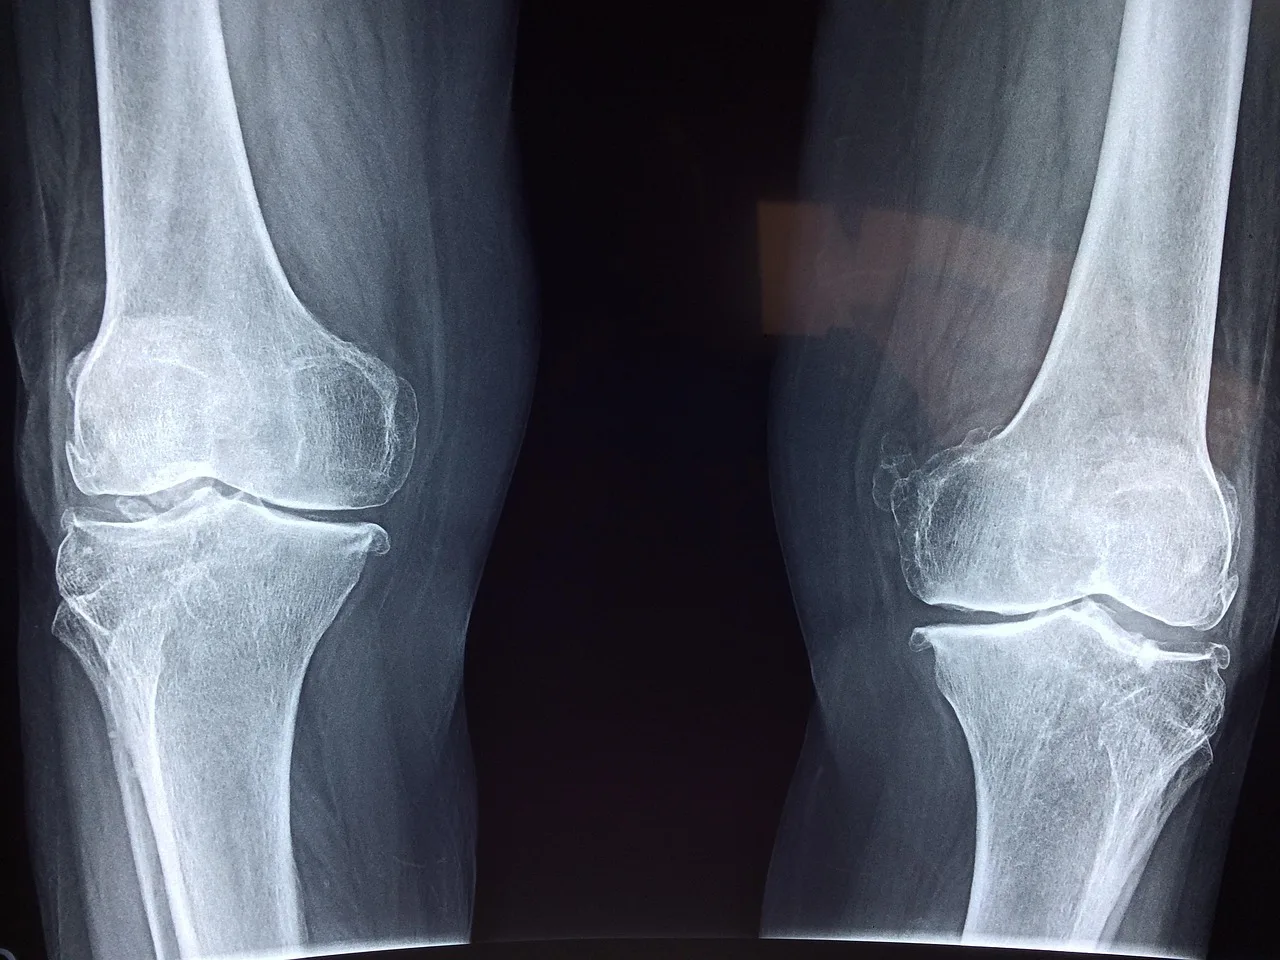

Knee Replacement Abroad: Complete 2025 Guide to Saving 70% on Surgery

Total knee replacement in the US costs $30,000-$50,000, but you can access world-class joint surgery abroad for $6,000-$12,000. This comprehensive guide covers the best countries, top surgeons, implant options, rehabilitation protocols, and real patient savings for knee replacement in 2025.